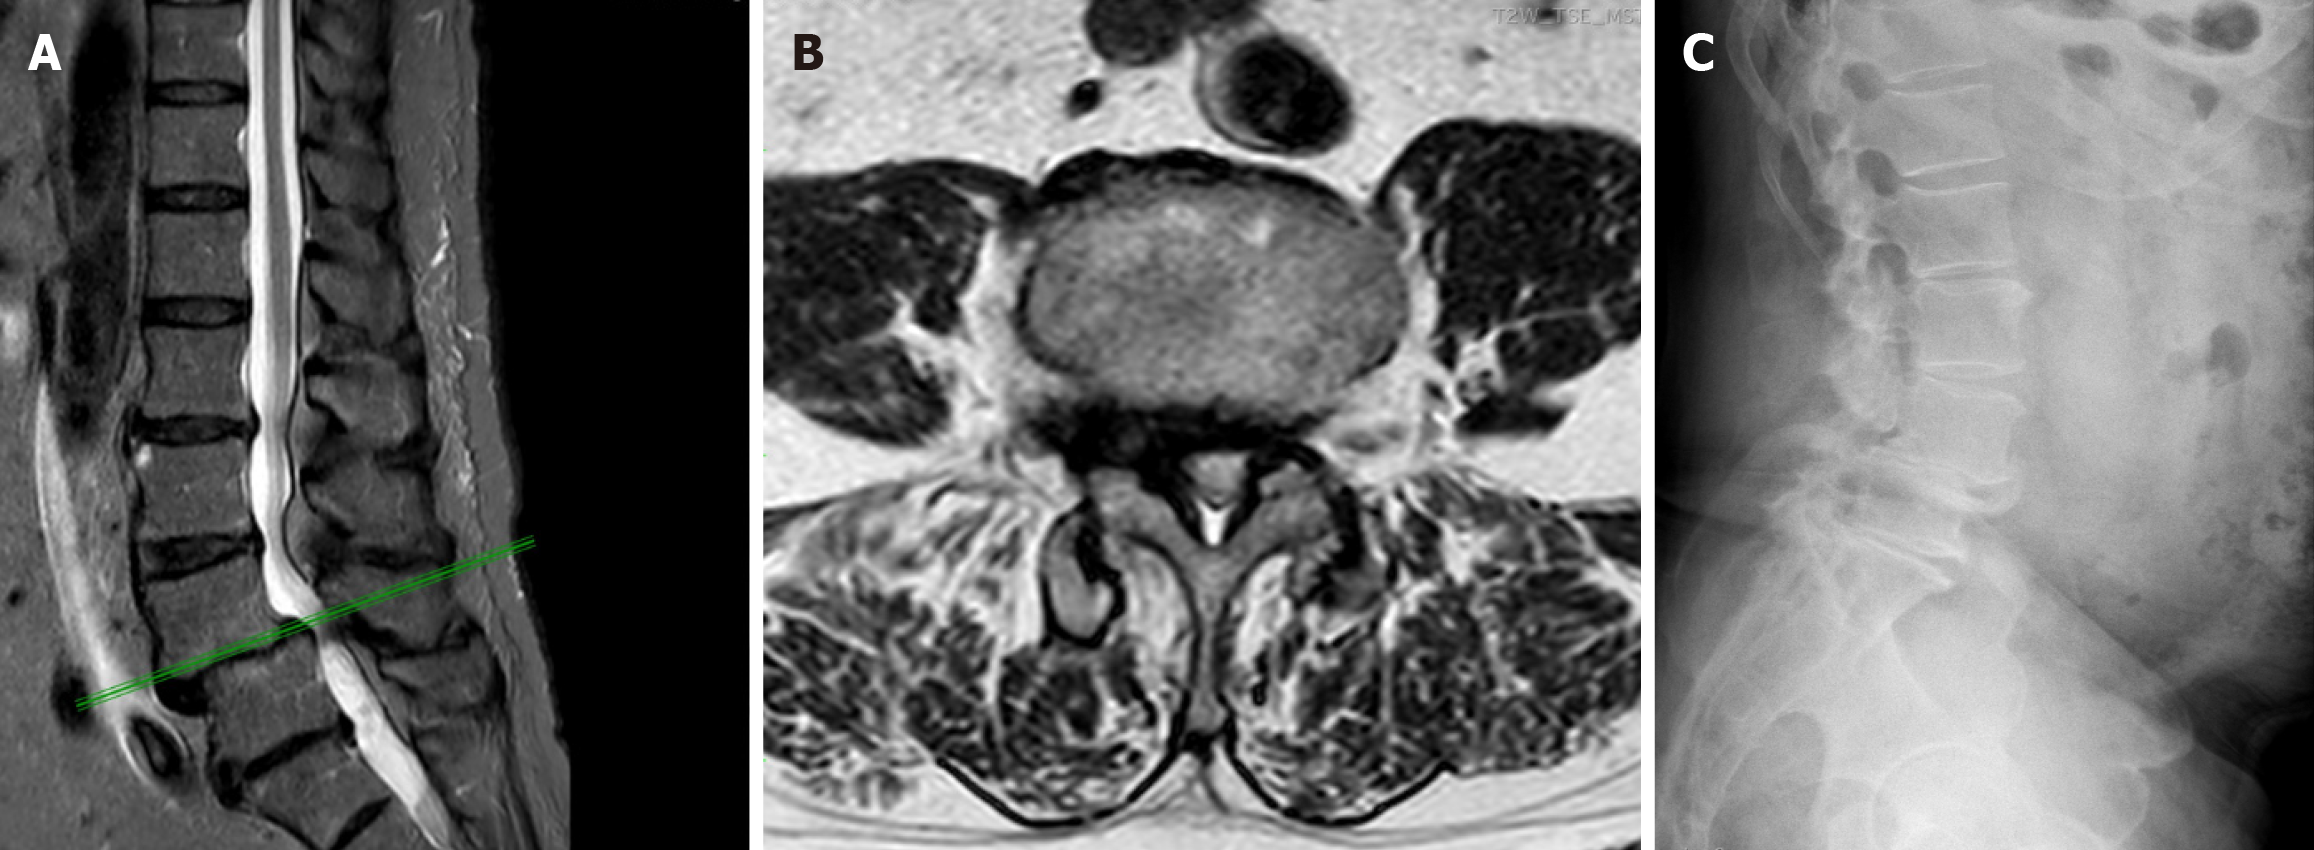

Facet joints serve as the posterior stabilizers of the spine and form part of the posterior border of the spinal canal. Degeneration of the facet joints with capsular laxity and loss of disc height can result in excessive motion and instability, while hypertrophic changes and osteophyte formation can result in a compressed spinal canal, leading to stenosis. These two conditions often coexist. Characteristic features like joint space narrowing, subchondral sclerosis, and osteophyte formation are seen on computed tomography or MRI[21]. As previously mentioned, facet arthropathy may also promote LF thickening or buckling due to reduced posterior tension[22]. In addition, intervertebral disc degeneration involves loss of disc height which shifts the mechanical load posteriorly and increases the strain on the facet joints and LF. Figure 2 shows examples of these degenerative changes that contributing to central canal stenosis and instability.

Figure 2

Figure 2 Imaging examples of degenerative changes contributing to central canal stenosis. A: Axial T2-weighted magnetic resonance imaging (MRI) from a 66-year-old male with unilateral facet joint hypertrophy (white arrow) narrowing the central canal; B: Sagittal T2-weighted MRI from a 49-year-old male showing ligamentum flavum thickening and buckling into the spinal canal (white arrows); C: Axial T2-weighted MRI from a 75-year-old male with lateral recess stenosis; D: Axial T2-weighted MRI from an 82-year-old male with central canal stenosis due to a combination of bilateral facet joint hypertrophy, ligamentum flavum thickening, and a central disc herniation.